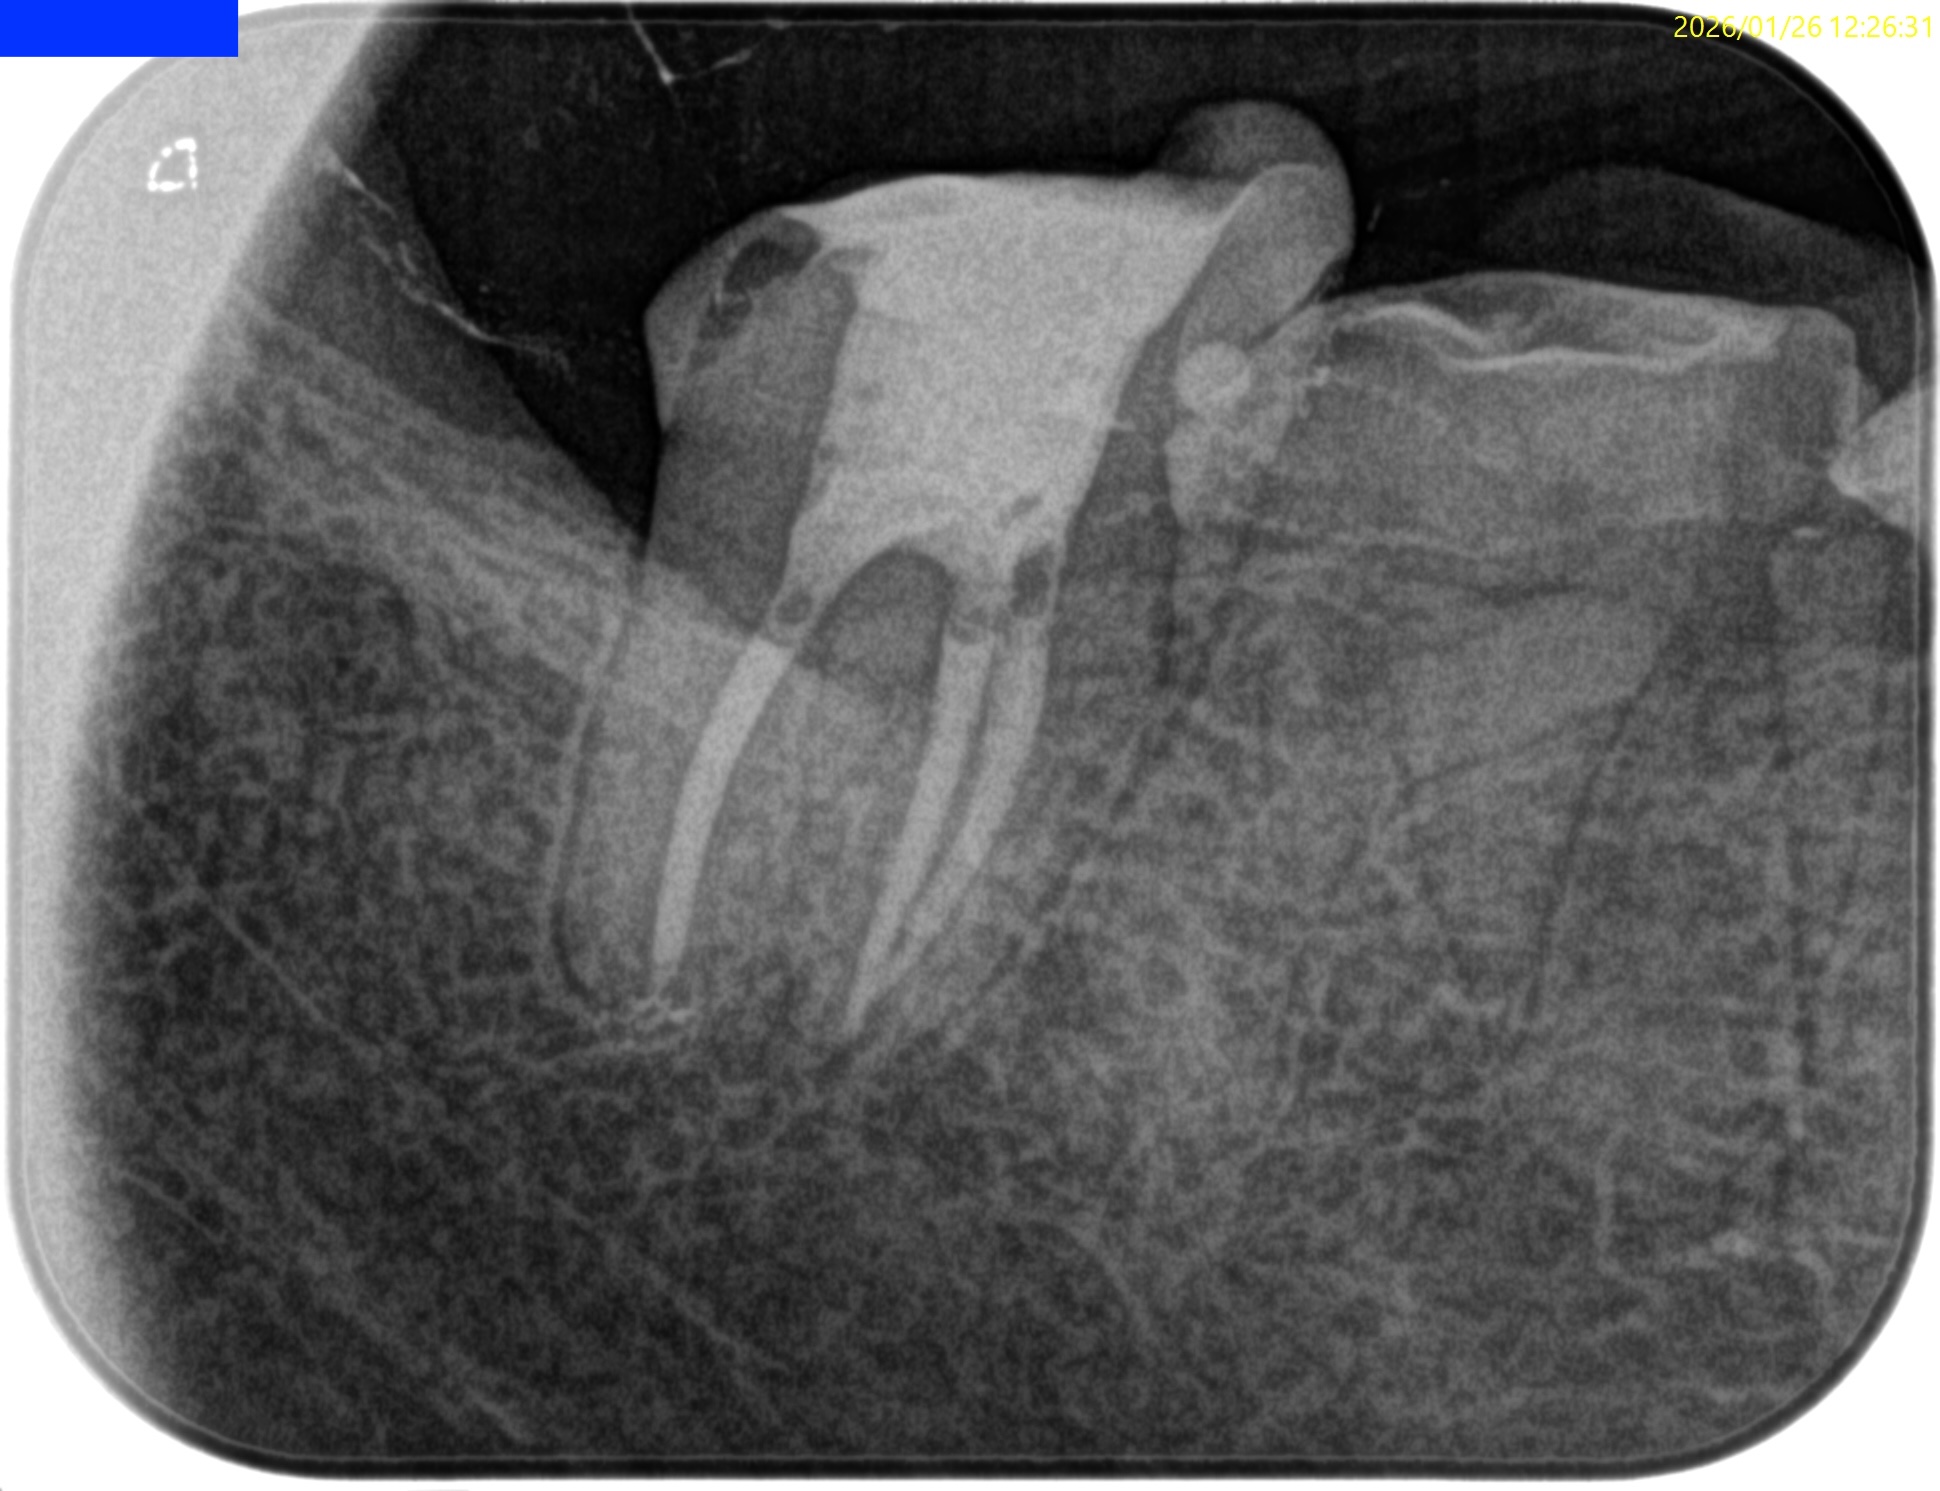

ML,MBは合流していることが多いと言う解剖学的情報をもとに以下のように合流部分をチェックした。

問題はないだろう。